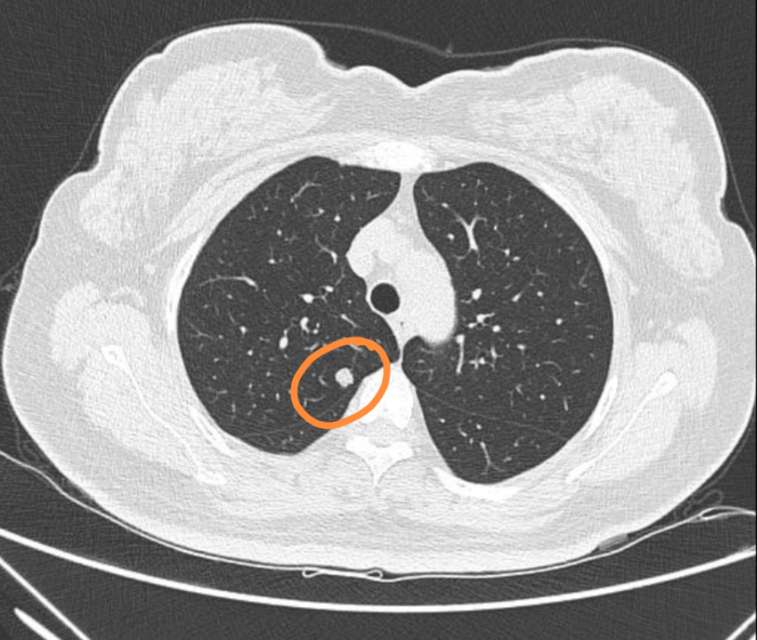

刘懿博士说肺癌二五九〇切之前知道俩肺结节是良性但不是一种病